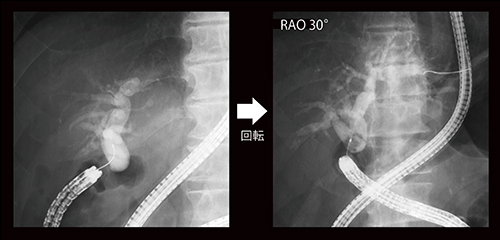

症例1は積み上げ結石症例で、正面では左右肝管合流部がほぼ描出されないが、RAO 22°回転で明瞭となった(図5)。

図5 症例1:積み上げ結石症例